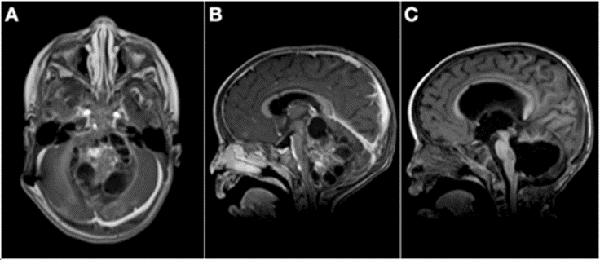

Figura 2: A) Paciente de 3 meses de vida, sexo masculino, consultó por macrocefalia e irritabilidad, IRM de cerebro con contraste EV donde se evidenció lesión intraventricular izquierda con extenso edema cerebral ipsilateral. Se realizó cirugía con exéresis parcial debido a labilidad hemodinámica. Anatomía patológica informó papiloma de plexos coroideos. B) IRM de cerebro 1 mes postquirúrgica. Se decidió diferir la re-exploración. C) Se realizó nueva cirugía luego de 6 meses. IRM de cerebro 1 mes post quirúrgica donde se constató la exéresis completa. Paciente evolucionó favorablemente, recuperó pautas madurativas pérdidas.

Figura 3: A) Paciente de 11 meses de vida, sexo masculino, que presentó macrocefalia, irritabilidad y vómitos, IRM de cerebro que mostró extensa lesión cerebelosa de aspecto nodular con intenso realce con el contraste endovenoso. B) IRM corte sagital de dicha lesión. C) IRM de cerebro postquirúrgica luego de dos cirugías de exploración y exéresis, diagnóstico de meduloblastoma desmoplásico nodular. Realizó quimioterapia y actualmente presenta un leve retraso neuromadurativo.

Figura 4: A) Paciente de 21 meses de vida, sexo masculino, que consultó por SHE y deterioro del sensorio. IRM de cerebro corte axial que evidenció lesión heterogénea en IV ventrículo y vermis con compromiso de tronco del encéfalo. B) IRM de cerebro corte sagital: ocupación de la totalidad del IV ventrículo. C) IRM de cerebro post quirúrgica, se evidenció exéresis tumoral completa, diagnóstico de ATRT de fosa posterior. Paciente falleció por progresion de enfermedad a los 6 meses.